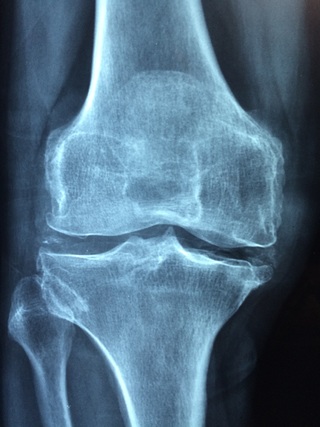

1. 관절에 좋다.

어떻게보면 보스웰리아를 사서 먹거나 구입하는데 가장 중요한 효능이죠. 보스웰리아에 들어 있는 보스웰릭산은 염증을 유발하는 물질의 활성을 억제시킨다고 합니다. 그래서 체네 연골 세포의 생존율을 높여서 관절염에 좋다고 알려져 있습니다. 그리고 보스웰릭산은 허리디스크, 무릎 연골 외상 등등의 예방에 좋은 효능을 보이고 있다고 합니다.